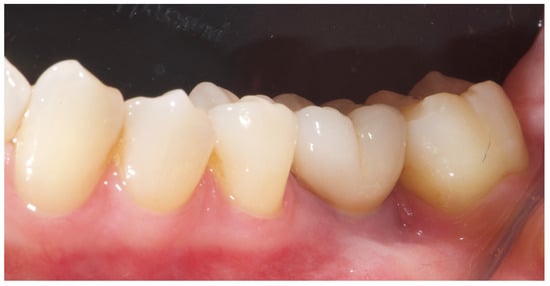

The patient entered a 6-month hygiene maintenance protocol and continues to be monitored. One year after definitive prosthesis delivery, the implants were clinically stable, with no bleeding on probing. Radiographically, the bone remains stable, with no bone loss (Figure 11).

Figure 11. One-year radiographic and clinical follow-up.